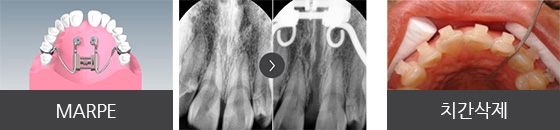

고르지 않은 앞니의 교정 치료를 위해 내원한 26세 여성입니다. 상대적으로 위턱의 공간이 아래턱에 비해 좁아 비대칭이 나타난 상황이었으나, 이를 빼거나 양악수술을 원치 않으셔서 그 대안으로 위턱뼈의 공간 확장 (MARPE)과 미니스크류를 이용하여 아래 치아를 후방 이동시킨 후 공간을 확보하는 치료 계획으로 진행되었습니다.

① 위턱의 골격적 확장을 위해 미니스크류를 이용한 급속구개확장장치(MARPE) 적용

② 교정용 미니스크류(miniscrew) 식립 및 사랑니가 있던 공간으로 어금니 후방 이동

발치와 양악수술 없이 자연스럽고 고른 치열을 갖게 되어 앞니의 심미적인 개선을 기대한 환자 분의 만족감이 높았습니다.